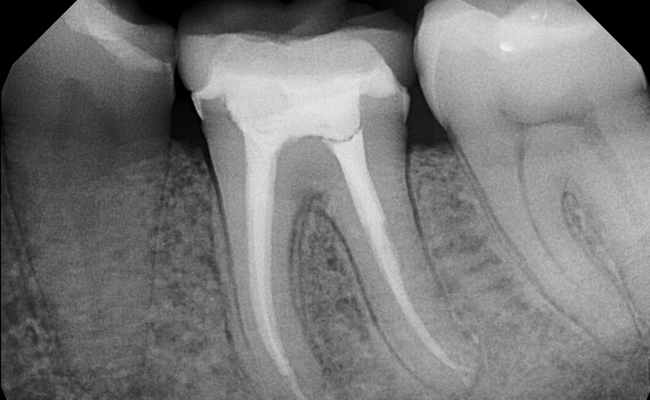

Root-Canal-Treatment

Root Canal Treatment

Also known as endodontic treatment done for the removal of infection from inside a tooth. It is carried out in the nerves present in pulp of the tooth, which is called as root canal. It is thought to be very painful but is a pain relieving treatment.